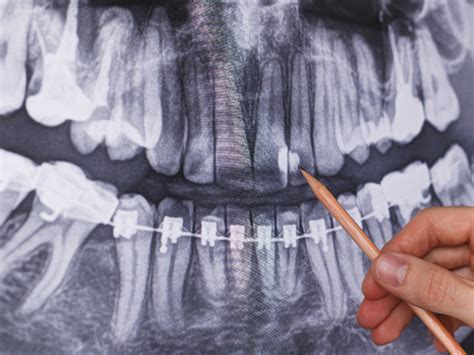

Tipos de Radiografías Utilizadas

- Radiografías de aleta de mordida: Son ideales para detectar caries interproximales.

- Radiografías periapicales: Permiten observar el diente completo, con las raíces y el hueso.

- Radiografías panorámicas: Ofrecen una visión general de toda la boca, útil para evaluar el estado general de los dientes y estructuras óseas.